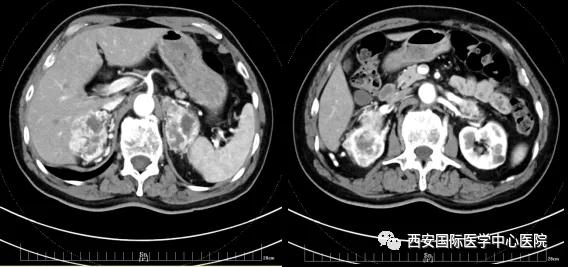

今年七十五歲的患者,來自陜西省商洛市,四月前因腰背部疼痛就診于當?shù)蒯t(yī)院,行CT檢查發(fā)現(xiàn)“右腎、雙側(cè)腎上腺占位,前縱膈淋巴結(jié)腫大,雙肺多發(fā)結(jié)節(jié)、胸椎骨質(zhì)破壞,考慮轉(zhuǎn)移瘤”。為進一步診斷治療,患者的兒子帶他來到西安某三甲醫(yī)院,查泌尿系CT提示“右腎占位性病變,多考慮腎癌,雙側(cè)腎上腺多發(fā)轉(zhuǎn)移灶,腹膜后多發(fā)腫大淋巴結(jié)”;行穿刺活檢提示“腎透明細胞癌”;并給予患者口服靶向藥物的治療方案。

自四月份至今,患者一直口服靶向藥物治療(阿昔替尼5mg 2次/日),期間無不良反應,目前腰背部疼痛癥狀也有所緩解,復查影像學資料提示瘤體較前縮小,腫瘤完整切除的可能性明顯提高;而且患者的兒子也是一名外科醫(yī)生,所以他更想為父親完成后續(xù)的手術(shù)治療。

患者一家慕名前來到西安國際醫(yī)學中心醫(yī)院找到楊增悅教授。楊增悅教授仔細看完患者的之前的影像學及病理資料后,診斷為:右腎透明細胞癌(T4N1M1);并安排他住院。而后,主管醫(yī)生及時為他完善了術(shù)前檢查及評估。7月15日,在麻醉手術(shù)中心柴偉主任、王彬榮副主任、李娟護士長、李瑞剛護士長及全體麻醉手術(shù)中心團隊的有力保障下,成功完成了這臺“大”手術(shù)。